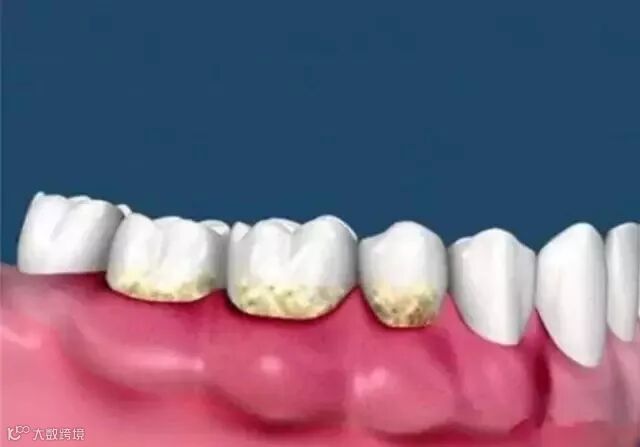

话说,我们的口腔每天都处在“水深火热”中,各种食物,各种冷饮、各种刺激..若你大快朵颐之后不收拾下口腔卫生,长期下来,就会堆积很多黄色的、棕色的甚至黑色的脏东西(牙结石)。

牙结石分为龈上结石和龈下结石,龈下的就没那么容易看得见了,也很难彻底清理,会刺激牙龈,造成牙龈发炎,糜烂,出血,加上牙周炎病人牙周袋较深,易堆积细菌,最后可能会导致牙齿脱落。